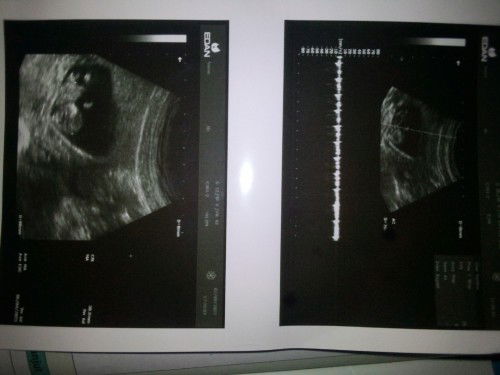

Kehamilan hasil USG

Bun mau tanya ..untuk lihat berat badan janin yg mana yaaa